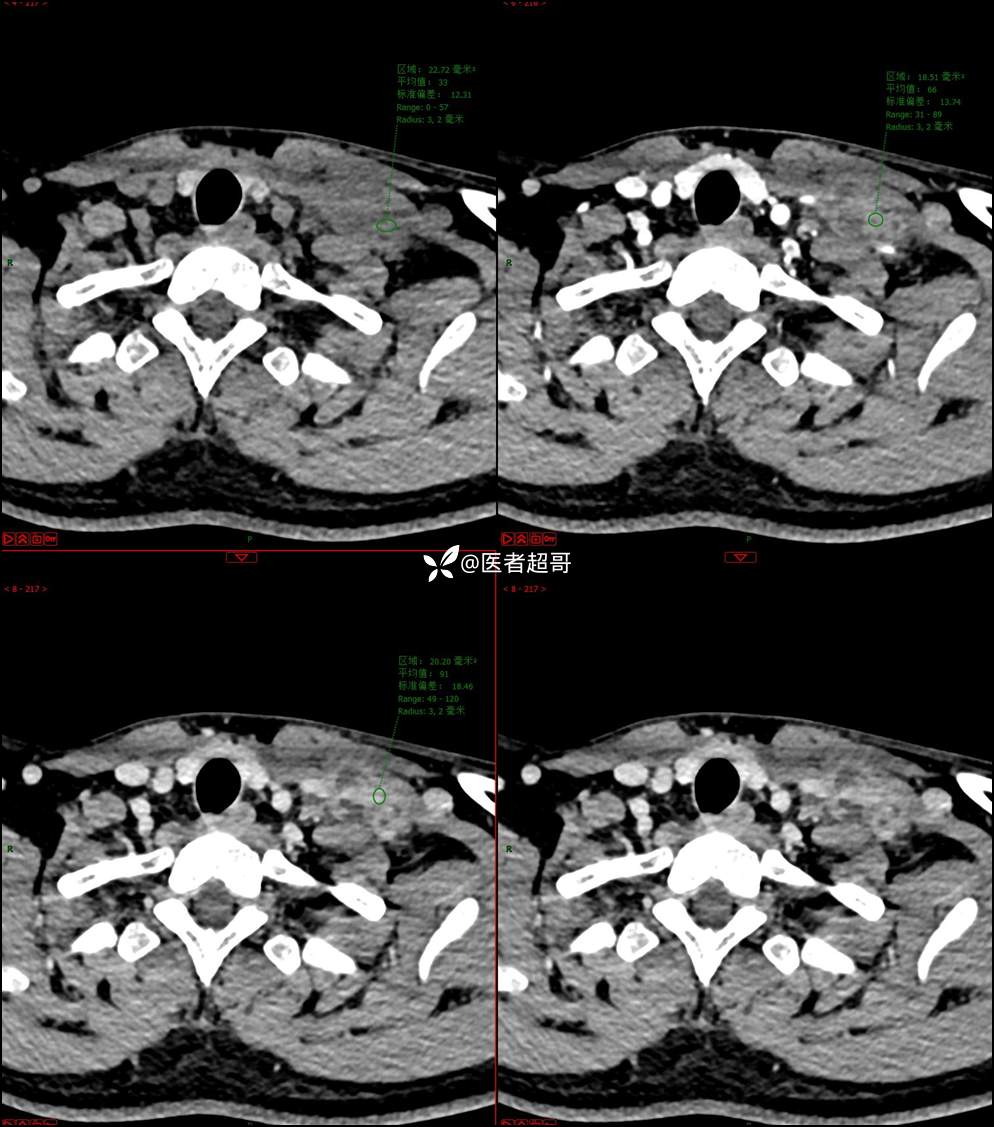

现病史:患者自述10余天前无意中发现左侧颈部一肿物,颈部活动时、进食时伴疼痛,无发热,患者前往人民医院就诊,给予输液治疗(头孢呋辛钠2g bid 硫酸阿米卡星0.4g qd、)10天,患者感肿物轻微变小,后患者为求进一步治疗,昨日来我院门诊就诊,给予颈部彩超示:左颈部实性肿物,神经来源?,左颈部肿大淋巴结;颈部ct平扫+强化示:左侧锁骨上区占位,神经鞘瘤?双侧颈部多发淋巴结;门诊以“局部肿物”收治入院,患者自患病以来,神志清,精神可,饮食睡眠可,体重无明显变化,二便正常。